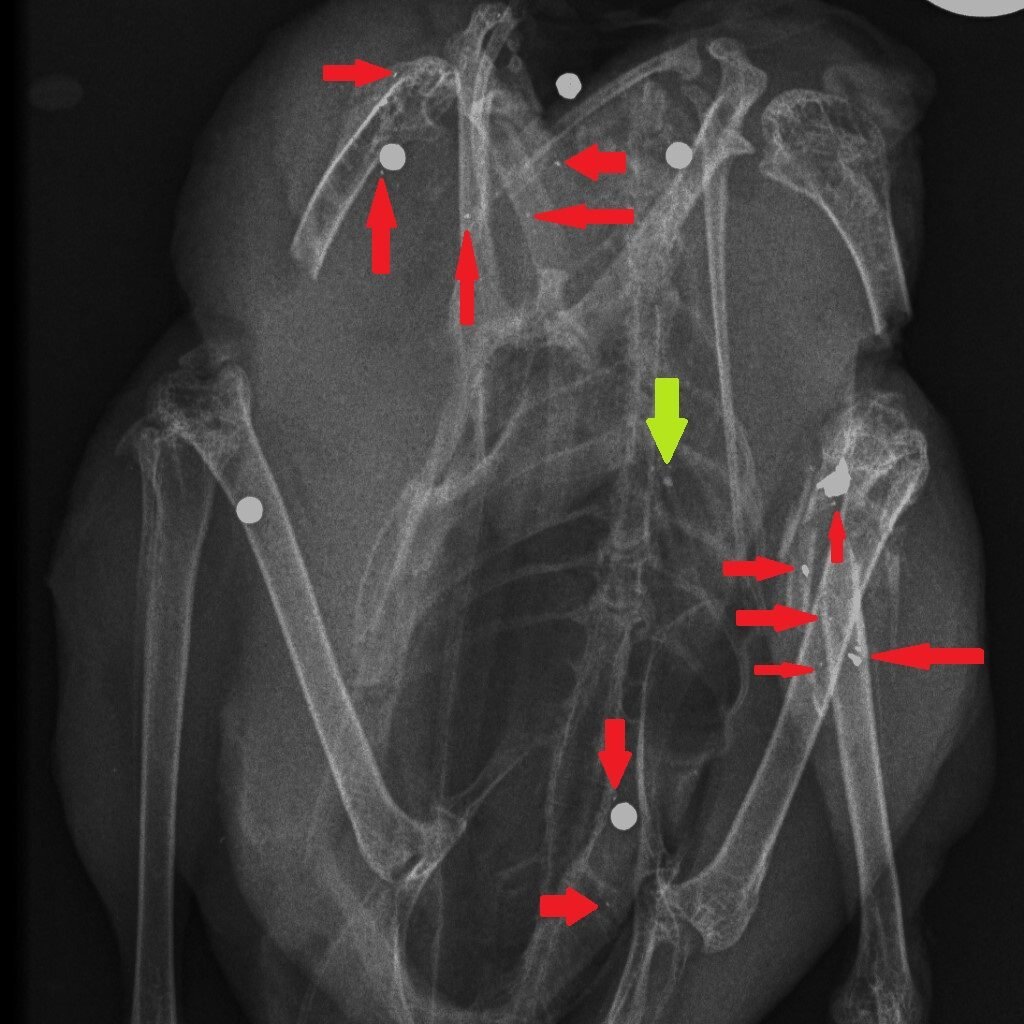

How could we reduce the risk of exposure to lead in game meat? It’s simple – stop shooting lead ammunition into animals that are destined for the human food chain. One of the useful properties of lead is that it is soft and malleable – that’s why, in the past, we have used it widely. But those same physical properties mean that lead passing through the flesh of a shot animal, hitting organs, soft tissue, bones and cartilage, shatters and tiny fragments of lead spread through the body of the animal. Here are three x-rays of shot birds that were bought in butcher’s shops and then x-rayed. The top x-ray is of a partridge and the other two are Red Grouse. Large white circular objects are lead shot. The green arrows point to fragments of bone and the red arrows indicate fragments of lead, from the shot, that have spread through the flesh.

Almost all of the fragments of lead are tiny – far too small to be detected in the cooking or eating process. Yes, you can spit out the almost-intact lead shot but you can’t get rid of the fragments. The lead analyses that have been done in studies cited above, and in our own, remove the lead shot and analyse the lead content of the meat after that removal. So when Sainsbury’s say that their game meat has no lead shot in it that’s good (although careful eating would remove those anyway) but they are not removing the tiny fragments of lead. So removing the almost intact lead shot particles is pretty irrelevant to the lead levels in the meat, as we will show you later this week…